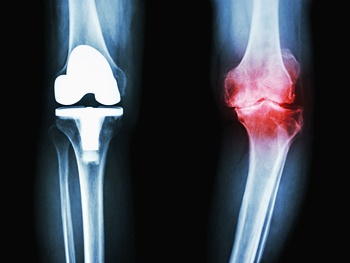

관절염 증상이 호전이 없고 변화가 진행되어 일상생활에 심한 지장을 줄 경우 시행됩니다. 관절경을 이용하여 관절 내부를 세척하고 유리체와 활액막 등을 제거하여 증상을 완화시키는데요. 통증이 적고 회복 기간이 빠른 장점이 있지만 완전한 치료가 되지는 않습니다. 절골술은 관절의 한 부분만 증상이 발생한 경우 관절 정렬을 바꾸어 주는 것을 말합니다. 이외에도 소파 관절 성형술, 다발성 천공술, 관절 성형술, 관절 고정술로 나누며 관절염의 발생 부위나 특성에 따라 다양한 수술적 치료를 진행할 수 있습니다.